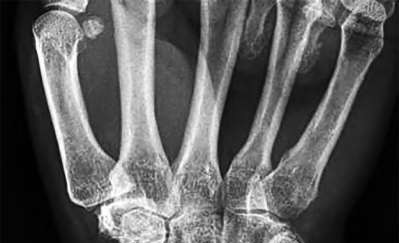

A 50-year-old woman is diagnosed with carpal tunnel syndrome. She is prescribed a cock-up wrist splint at 30 degrees of extension to wear at night. This splint has what effect on the carpal tunnel?